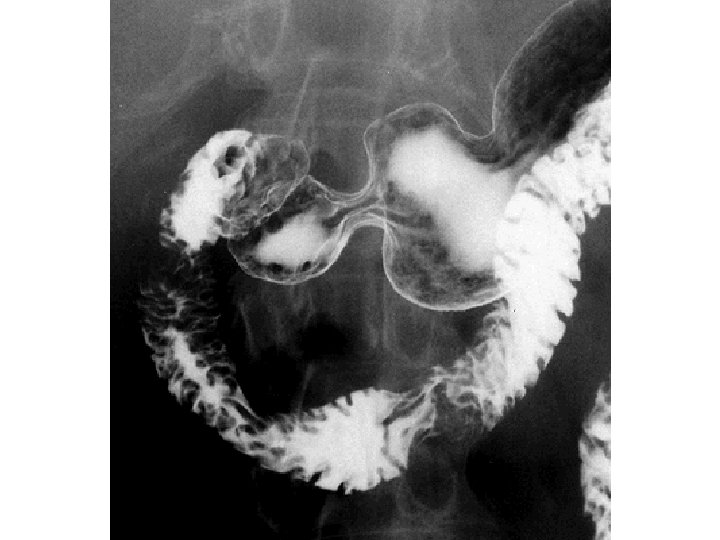

Irigography